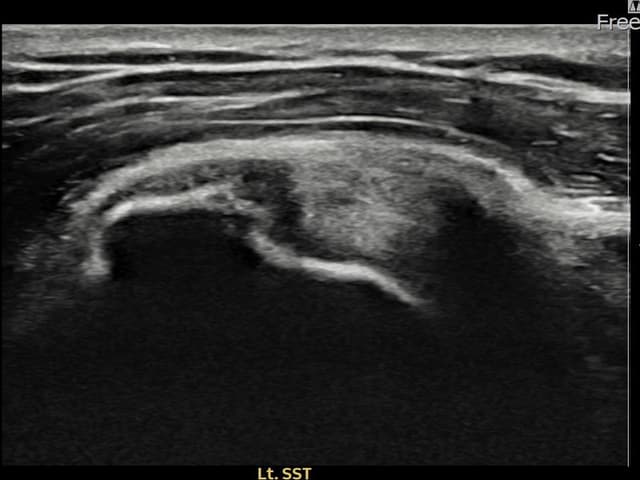

[촬영시기:22.10.06~22.11.14]

[어깨인대 축소봉합술] 좌측 어깨 극상근건 광범위 파열로 수개월간 일상생활이 어렵던 중 내원하셨습니다.